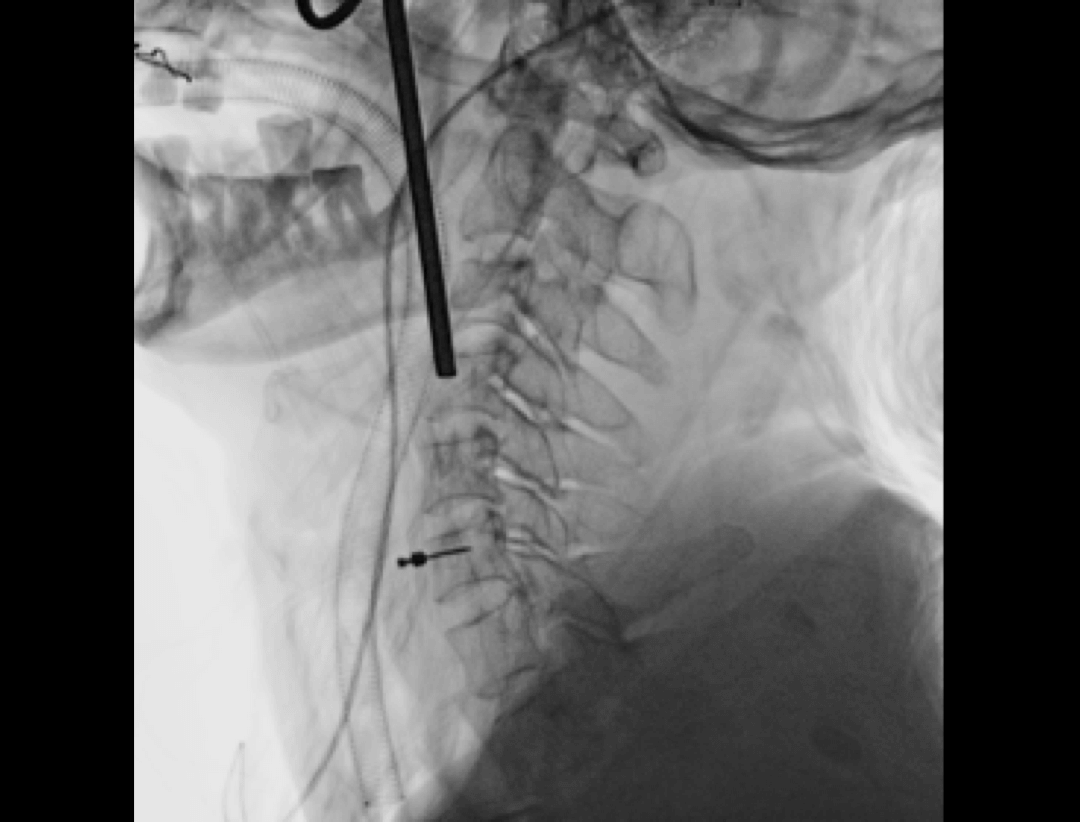

Przednia discektomia szyjna